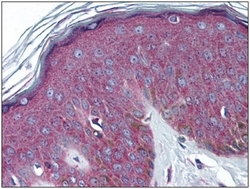

Supportive validation

- Submitted by

- OriGene (provider)

- Main image

- Experimental details

- Human Skin: Formalin-Fixed, Paraffin-Embedded (FFPE)

- Validation comment

- IHC